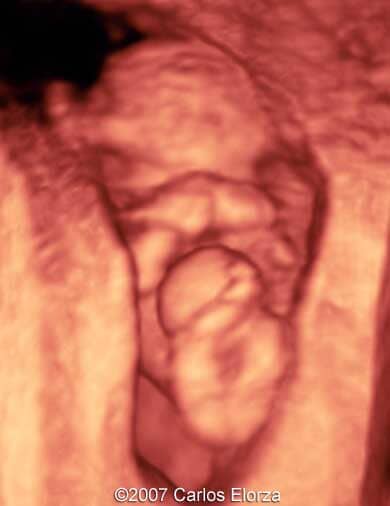

38-year-old woman (G3, P2)Ā presented in our department at 10th week of pregnancy. Ultrasound examination discovered striking nuchal edema and omphalocele with liver"s exenteration. A chorionic biopsy revealed trisomy 13. Here are someĀ images that we obtained.